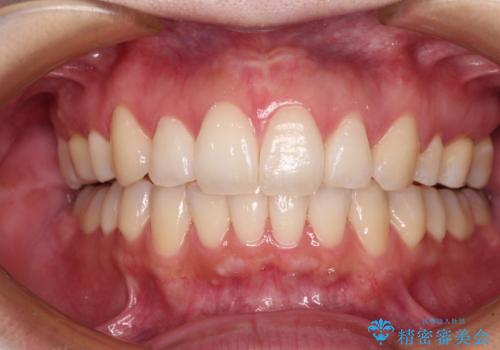

ディープバイトや奥歯の咬み合わせなど、インビザライン矯正では限界がありワイヤー装置での治療に及ばない仕上がりとなりました。

ただし、患者様としては八重歯や、それに伴う唇の閉じにくさが改善されたとのことで、納得いく状態での治療終了となりました。